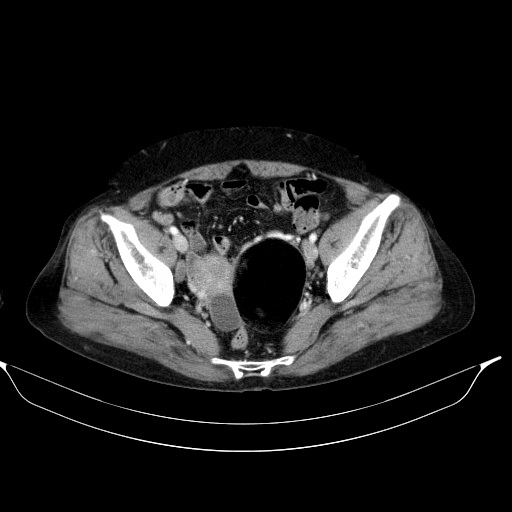

CT영상에서 우측난소에 단순낭종이 보입니다.

산부인과에서 촬영했던 질초음파영상에서 보였던 uterine myoma소견도 확인됩니다.

여기까지 봐도 질초음파영상에서 봤던 크기가 큰 낭성병변이 CT에서는 보이지 않았기에 방광을 낭성병변으로 본 게 아닌가 하는 의심을 가지고, 다시 질초음파 및 복부초음파를 시행했지만, 여전히 위에서 보여준 커다란 낭성병변이 존재하고, 소변을 다 본 상태에서도 전혀 변함없이 병변이 확인되는 거였습니다.

이쯤에서 이미 눈치채신 분들이 많겠지만, 앞서 CT 영상에서도 병변이 보이는데 그걸 놓치고 병변이 없다고 잘못 판단한 사례였습니다.

공기음영과 구분이 되지 않을 정도로 저음영을 보이는 fat-attenuated cyst가 자궁과 우측난소를 오른쪽으로 밀고 있었는데, 주변 장기들의 위치변화와 윤곽을 미처 확인하지 못하고 fat이 아닌 직장내 공기음영으로 잠시 착각했던 겁니다.